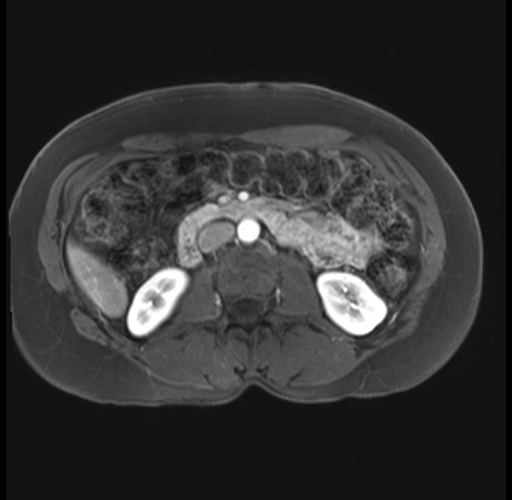

Imaging Analysis

Look through the patient's CT scan to identify any areas of concern for the necessary procedure.

Based on your CT findings, which issue(s) are present and would give reason for "planned slowing down moment(s)" in this case?

Considering a standard distal pancreatectomy procedure, what step(s) of the operation would you do differently in this case?